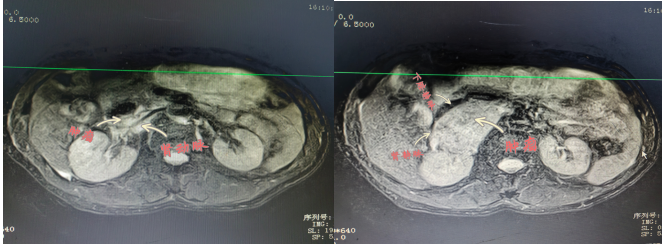

患者陽某,67歲,8月2日因“反復(fù)胸悶氣促2年余,再發(fā)伴頭暈黑蒙3天?!本驮\于衡陽市中心醫(yī)院心血管內(nèi)科,患者血壓波動大,最高值199/118mmHg,最小值98/57mmHg,射血分?jǐn)?shù)最低42%;完善相關(guān)檢查發(fā)現(xiàn)右腎上腺巨大腫物,大小約57×73×75mm,遂轉(zhuǎn)入衡陽市中心醫(yī)院泌尿外科治療,泌尿外科醫(yī)護(hù)團(tuán)隊前期做了充分的準(zhǔn)備,并進(jìn)行科內(nèi)討論,麻醉科、心血管內(nèi)科專家會診,充分予以穩(wěn)定血壓、心率和擴(kuò)容等術(shù)前處理。

2022年9月15日,醫(yī)院為患者行腹腔鏡下右側(cè)腎上腺瘤腫瘤切除術(shù),術(shù)中,患者右側(cè)腎上腺腫瘤于腎門,壓迫下腔靜脈,右腎靜脈移位,包繞右腎動脈。腫瘤體積大,血運豐富與周圍組織邊界不清, 與大血管粘連,手術(shù)風(fēng)險極大,術(shù)中鉗夾,擠壓腎上腺瘤體導(dǎo)致腎上腺激素釋放,手術(shù)中血壓的急劇變化。充分顯露手術(shù)視野,仔細(xì)、輕柔操作對腫瘤切除十分關(guān)鍵。麻醉科主任譚滇湘全程護(hù)航。由于準(zhǔn)備充分、配合到位,雖術(shù)中情況多變,最終手術(shù)成功。術(shù)后病檢結(jié)果顯示腫瘤完整切除?;颊咝g(shù)后恢復(fù)良好,于2022年9月24康復(fù)出院。